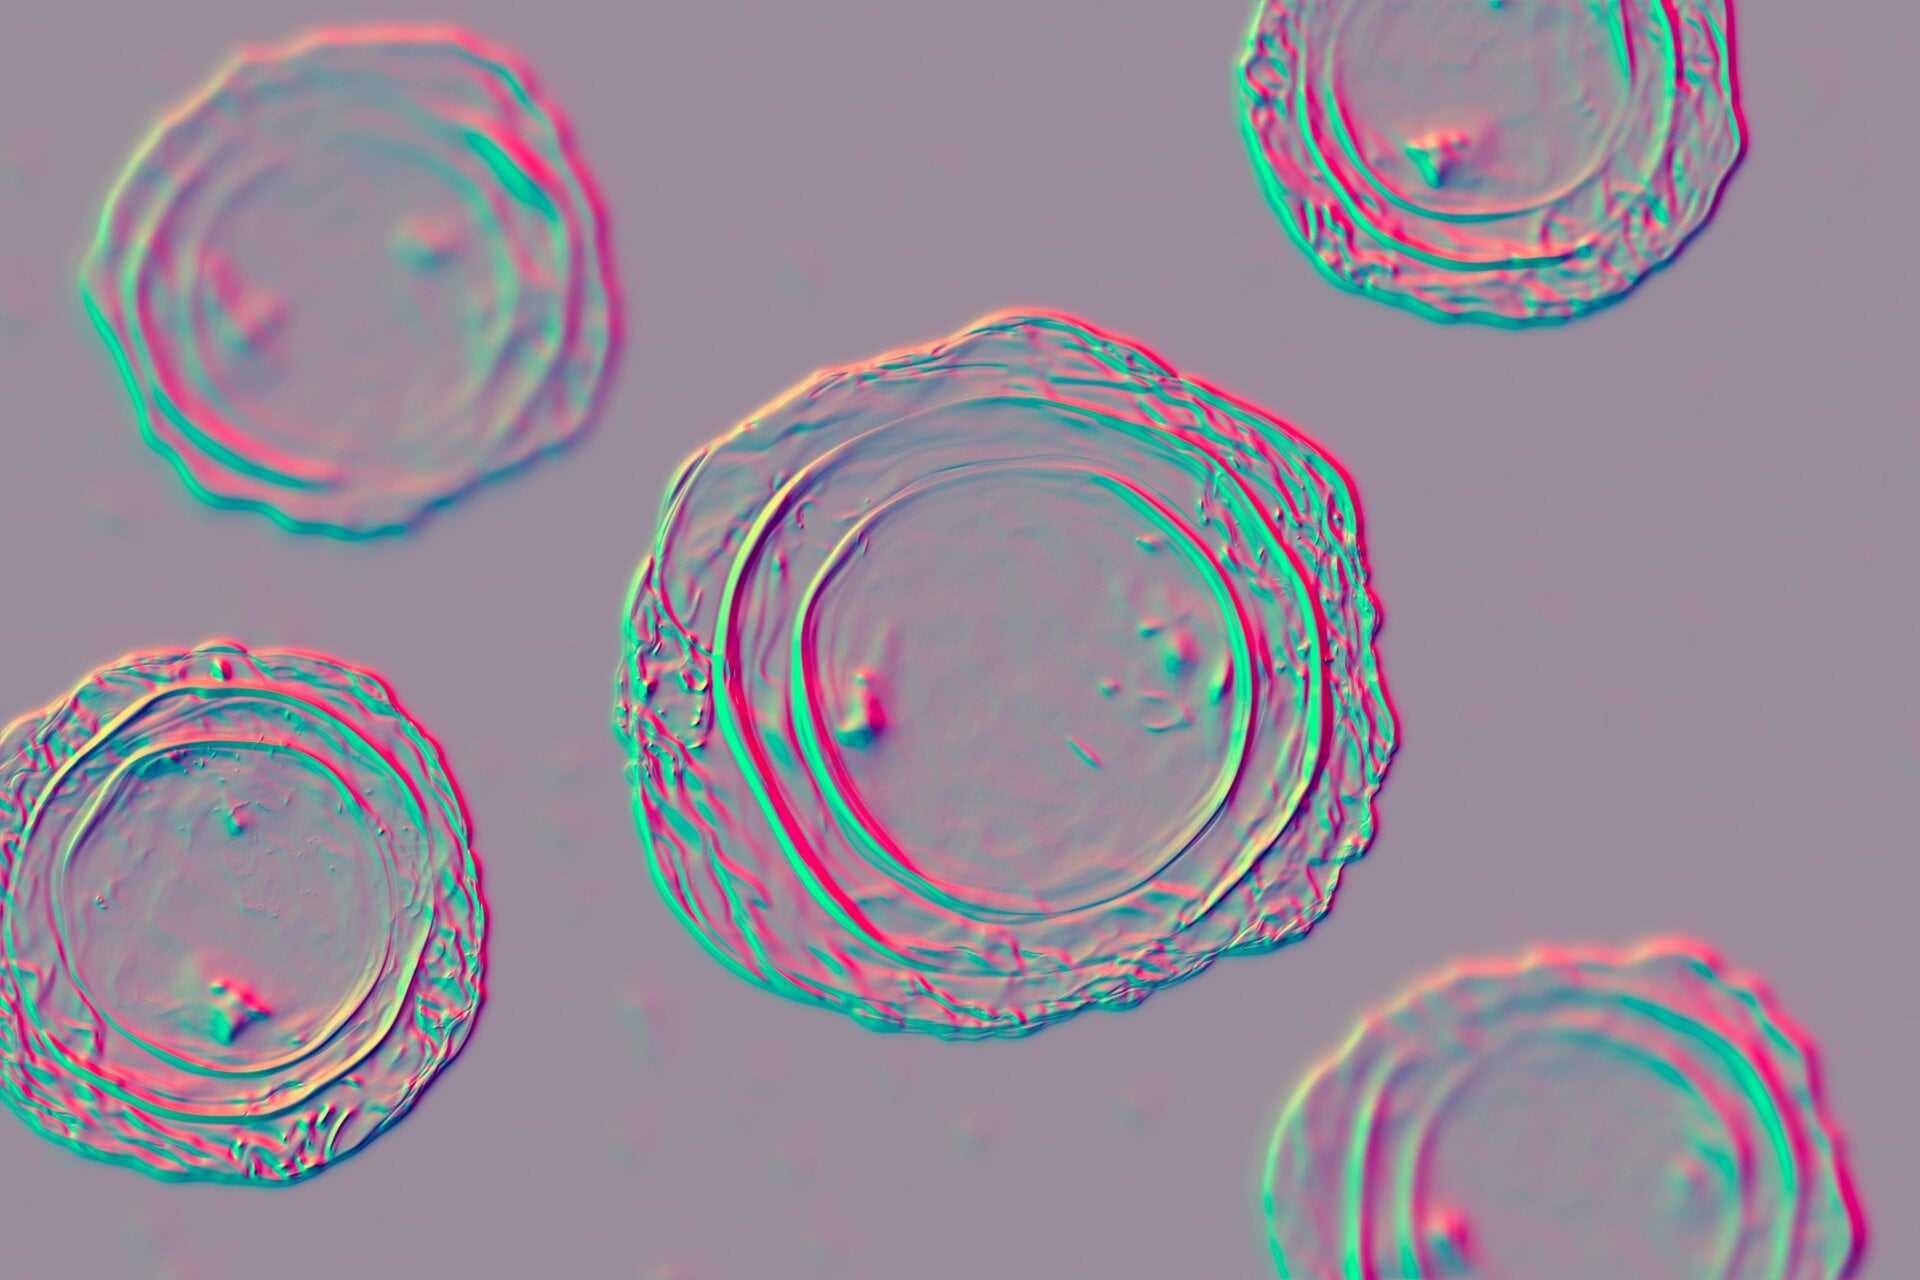

áscaris

Estos tipos son otro tipo de lombrices intestinales que puedes atrapar en la playa o en el suelo en general. áscaris Las infecciones son en realidad los parásitos más comunes transmitidos por el suelo en humanos, con hasta mil millones de personas en todo el mundo. actualmente pensado para llevarlos. La gente generalmente contrae estos gusanos al ingerir o tocar tierra o agua contaminada por las heces infectadas de otra persona. Afortunadamente, áscaris Las infecciones son relativamente poco comunes en los EE. UU.